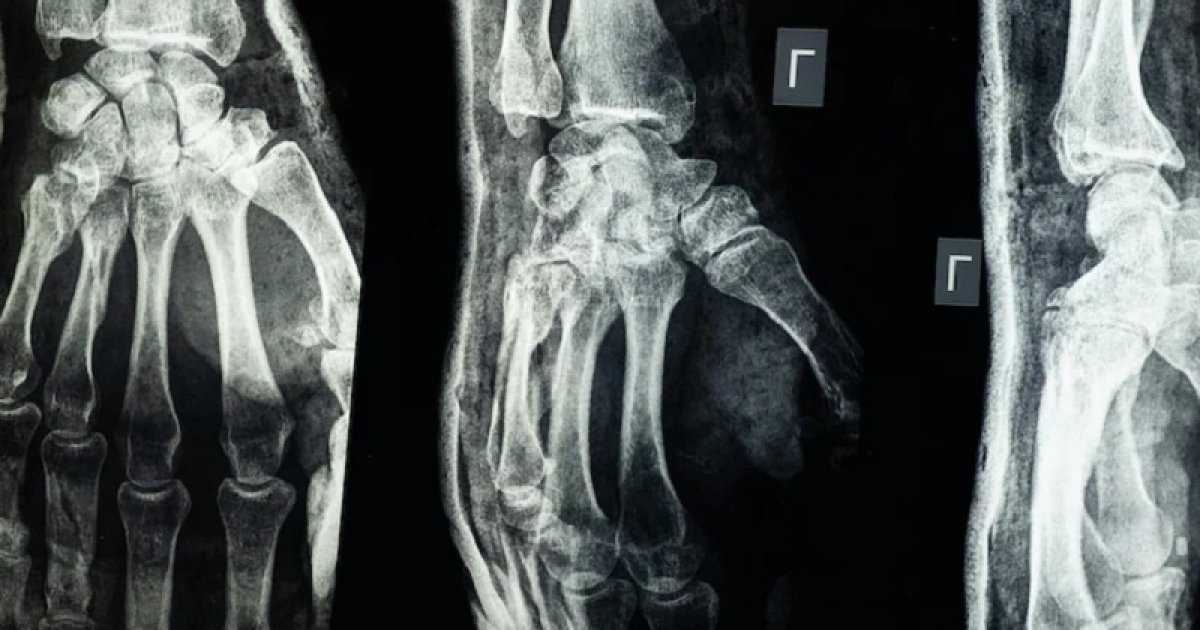

মাত্র তিন মিনিটের মধ্যেই ভাঙা বা টুকরো টুকরো হয়ে যাওয়া হাড় জোড়া দিতে সক্ষম গ্লু তৈরি করেছেন চীনা বিজ্ঞানীরা। এর নাম ‘বোন গ্লু’। দীর্ঘদিন ধরেই চিকিৎসা বিজ্ঞানে হাড় জোড়া দেওয়ার জন্য কার্যকর আঠা আবিষ্কারকে ‘স্বপ্নের আবিষ্কার’ বলা হতো। এবার চীনা বিজ্ঞানীরা সেটি বাস্তবে রূপ দিয়েছেন বলে মনে করা হচ্ছে।

বোন-০২ নামের এই আঠা উন্মোচন করেছে চীনের ঝেজিয়াং প্রদেশের একটি গবেষণা দল। গবেষণা দলের নেতা ও স্যার রান রান শ’ হাসপাতালের সহযোগী প্রধান অর্থোপেডিক সার্জন লিন জিয়ানফেং জানিয়েছেন, ঝিনুক যেভাবে পানির নিচে সেতুর গায়ে শক্তভাবে আটকে থাকতে পারে, সেটিই তাকে এই আঠা তৈরির অনুপ্রেরণা দিয়েছে।

ডা. লিন জানান, এই আঠা রক্তমাখা ভেজা পরিবেশেও দুই থেকে তিন মিনিটের মধ্যে হাড়কে সঠিকভাবে স্থির করতে পারে। আরও বড় সুবিধা হলো, এটি শরীরে ধীরে ধীরে শোষিত হয়ে যায়। ফলে প্রচলিত ধাতব প্লেট বা স্ক্রুর মতো আবার অপারেশন করে সরাতে হয় না।

ল্যাব পরীক্ষায় দেখা গেছে, বোন-০২ নিরাপত্তা ও কার্যকারিতা উভয় ক্ষেত্রেই সফল হয়েছে। এক পরীক্ষায় ১৮০ সেকেন্ডের কম সময়ে প্রক্রিয়া সম্পন্ন হয়, যেখানে প্রচলিত চিকিৎসায় বড় কেটে ধাতব প্লেট-স্ক্রু বসাতে হতো।

পরীক্ষায় দেখা গেছে, আঠা দিয়ে জোড়া দেওয়া হাড় সর্বোচ্চ ৪০০ পাউন্ড পর্যন্ত চাপ সহ্য করেছে, শিয়ার স্ট্রেংথ ছিল প্রায় ০.৫ এমপিএ এবং কম্প্রেশন স্ট্রেংথ প্রায় ১০ এমপিএ।

গবেষকদের দাবি, এই ক্ষমতা ভবিষ্যতে ধাতব ইমপ্ল্যান্টের বিকল্প হিসেবে কাজ করতে পারে এবং সংক্রমণ বা শরীরের প্রতিক্রিয়ার ঝুঁকিও কমাতে পারে।